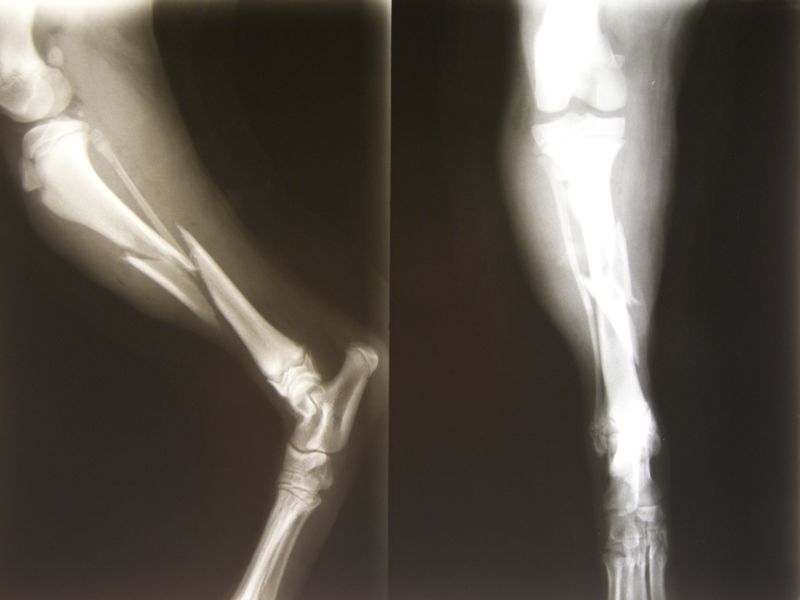

Urgentna služba Javne zdravstvene ustanove “Zdravstveni centar Brčko”, u posljednjih sedam dana, registrovala je dvadesetak pacijenata koji su zbog padova imali prelome.

«Ovaj broj je nešto veći u odnosu na dane bez snijega, no broj povreda nije alarmantan. Riječ je uglavnom o prelomima skočnog i zgloba šake zbog činjenice da ljudi nastoje ublažiti pad dočekujući se na dlanove», rekla je dežurna doktorica Urgentne službe, Ljiljana Petrić.